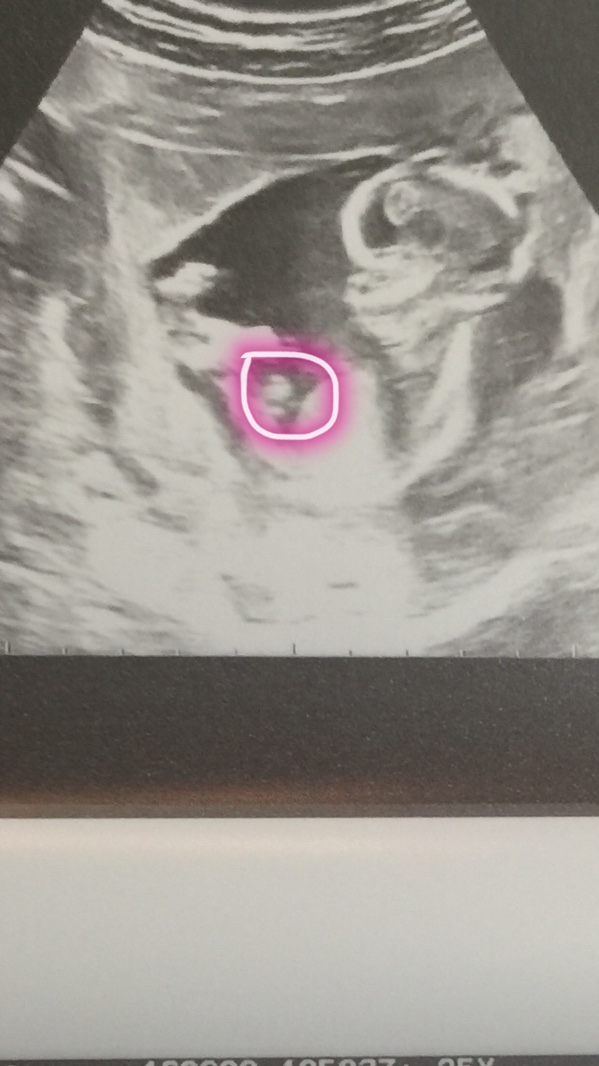

7)

看我圈的部分,那个小肿块,上翘30度可能是男孩,平的是女孩。(觉得这个很准,有经验的医生也是*JJ看**部分小肿块吧?)